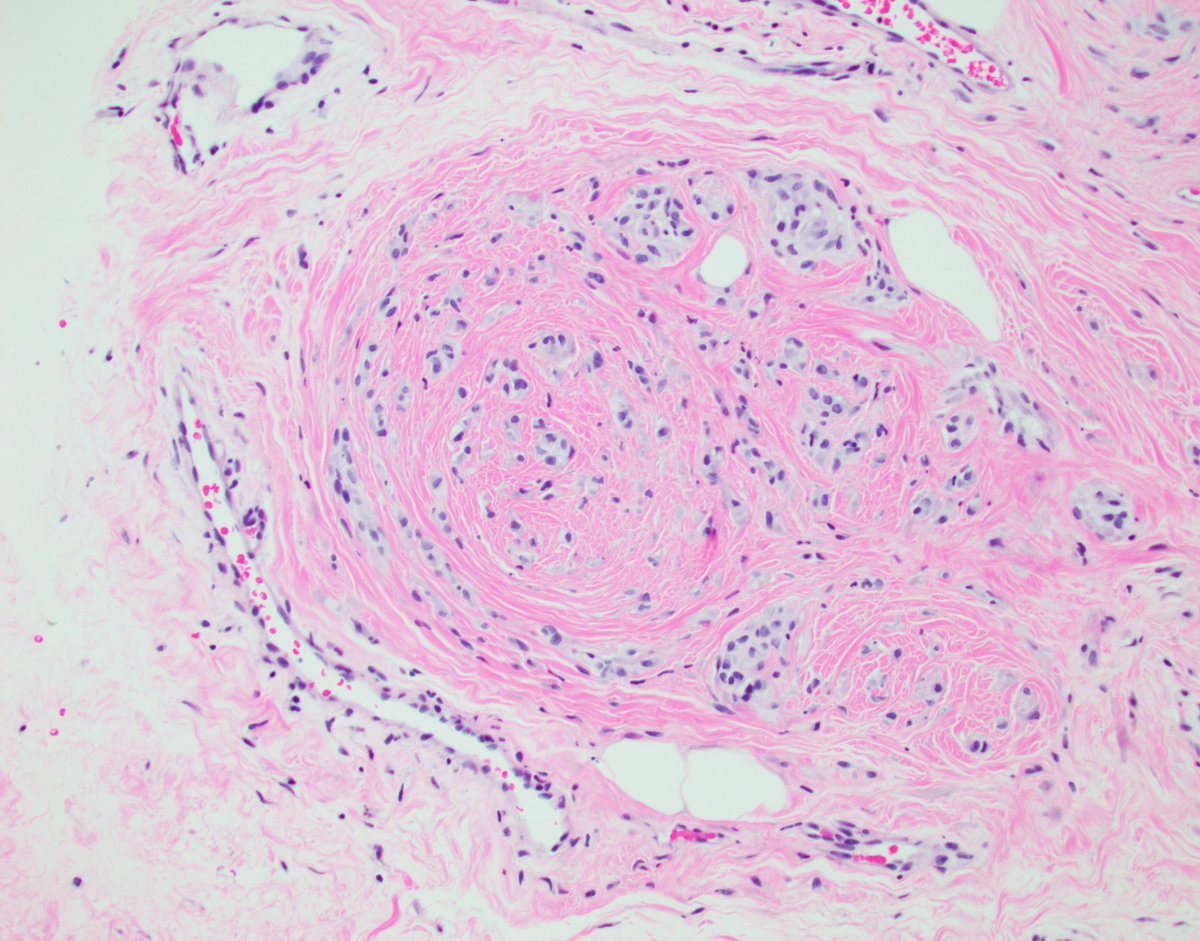

Behind the pink ribbon, thereโ€™s a story only a histopathologist can reveal. *Early detection saves lives*. ๐Ÿ’• #PinkOctober #BehindTheScenesOfBreastCancerDiagnosis #BreastCancerAwarenessMonth #breastpath